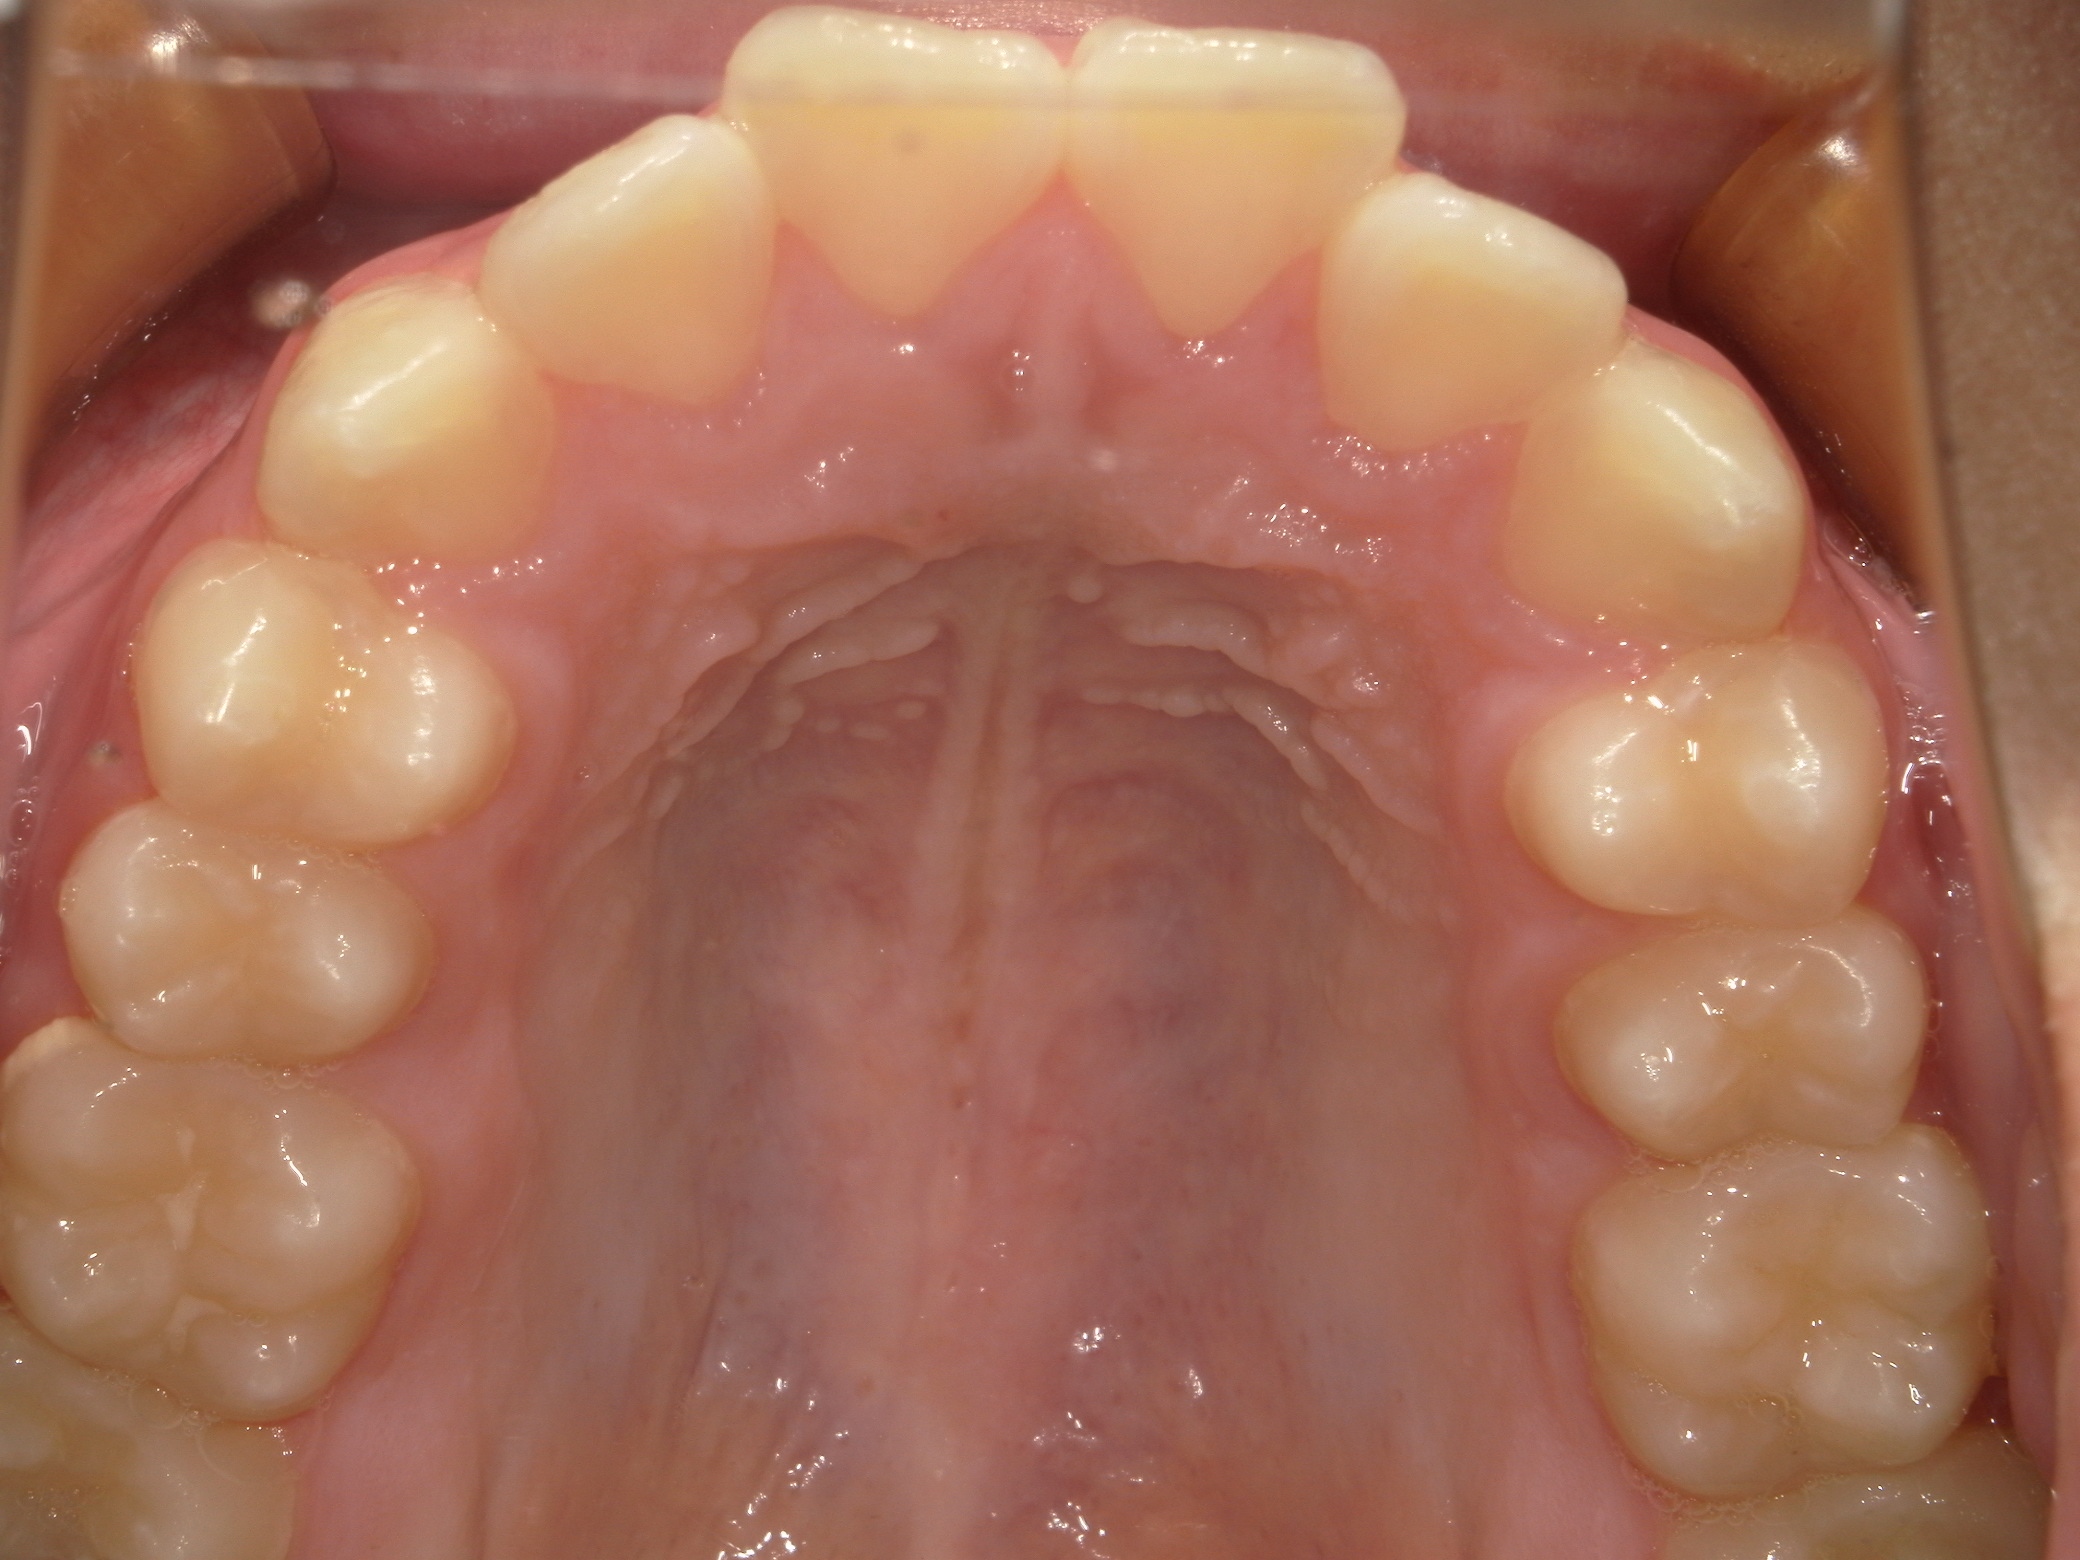

口内上

治療前

治療後